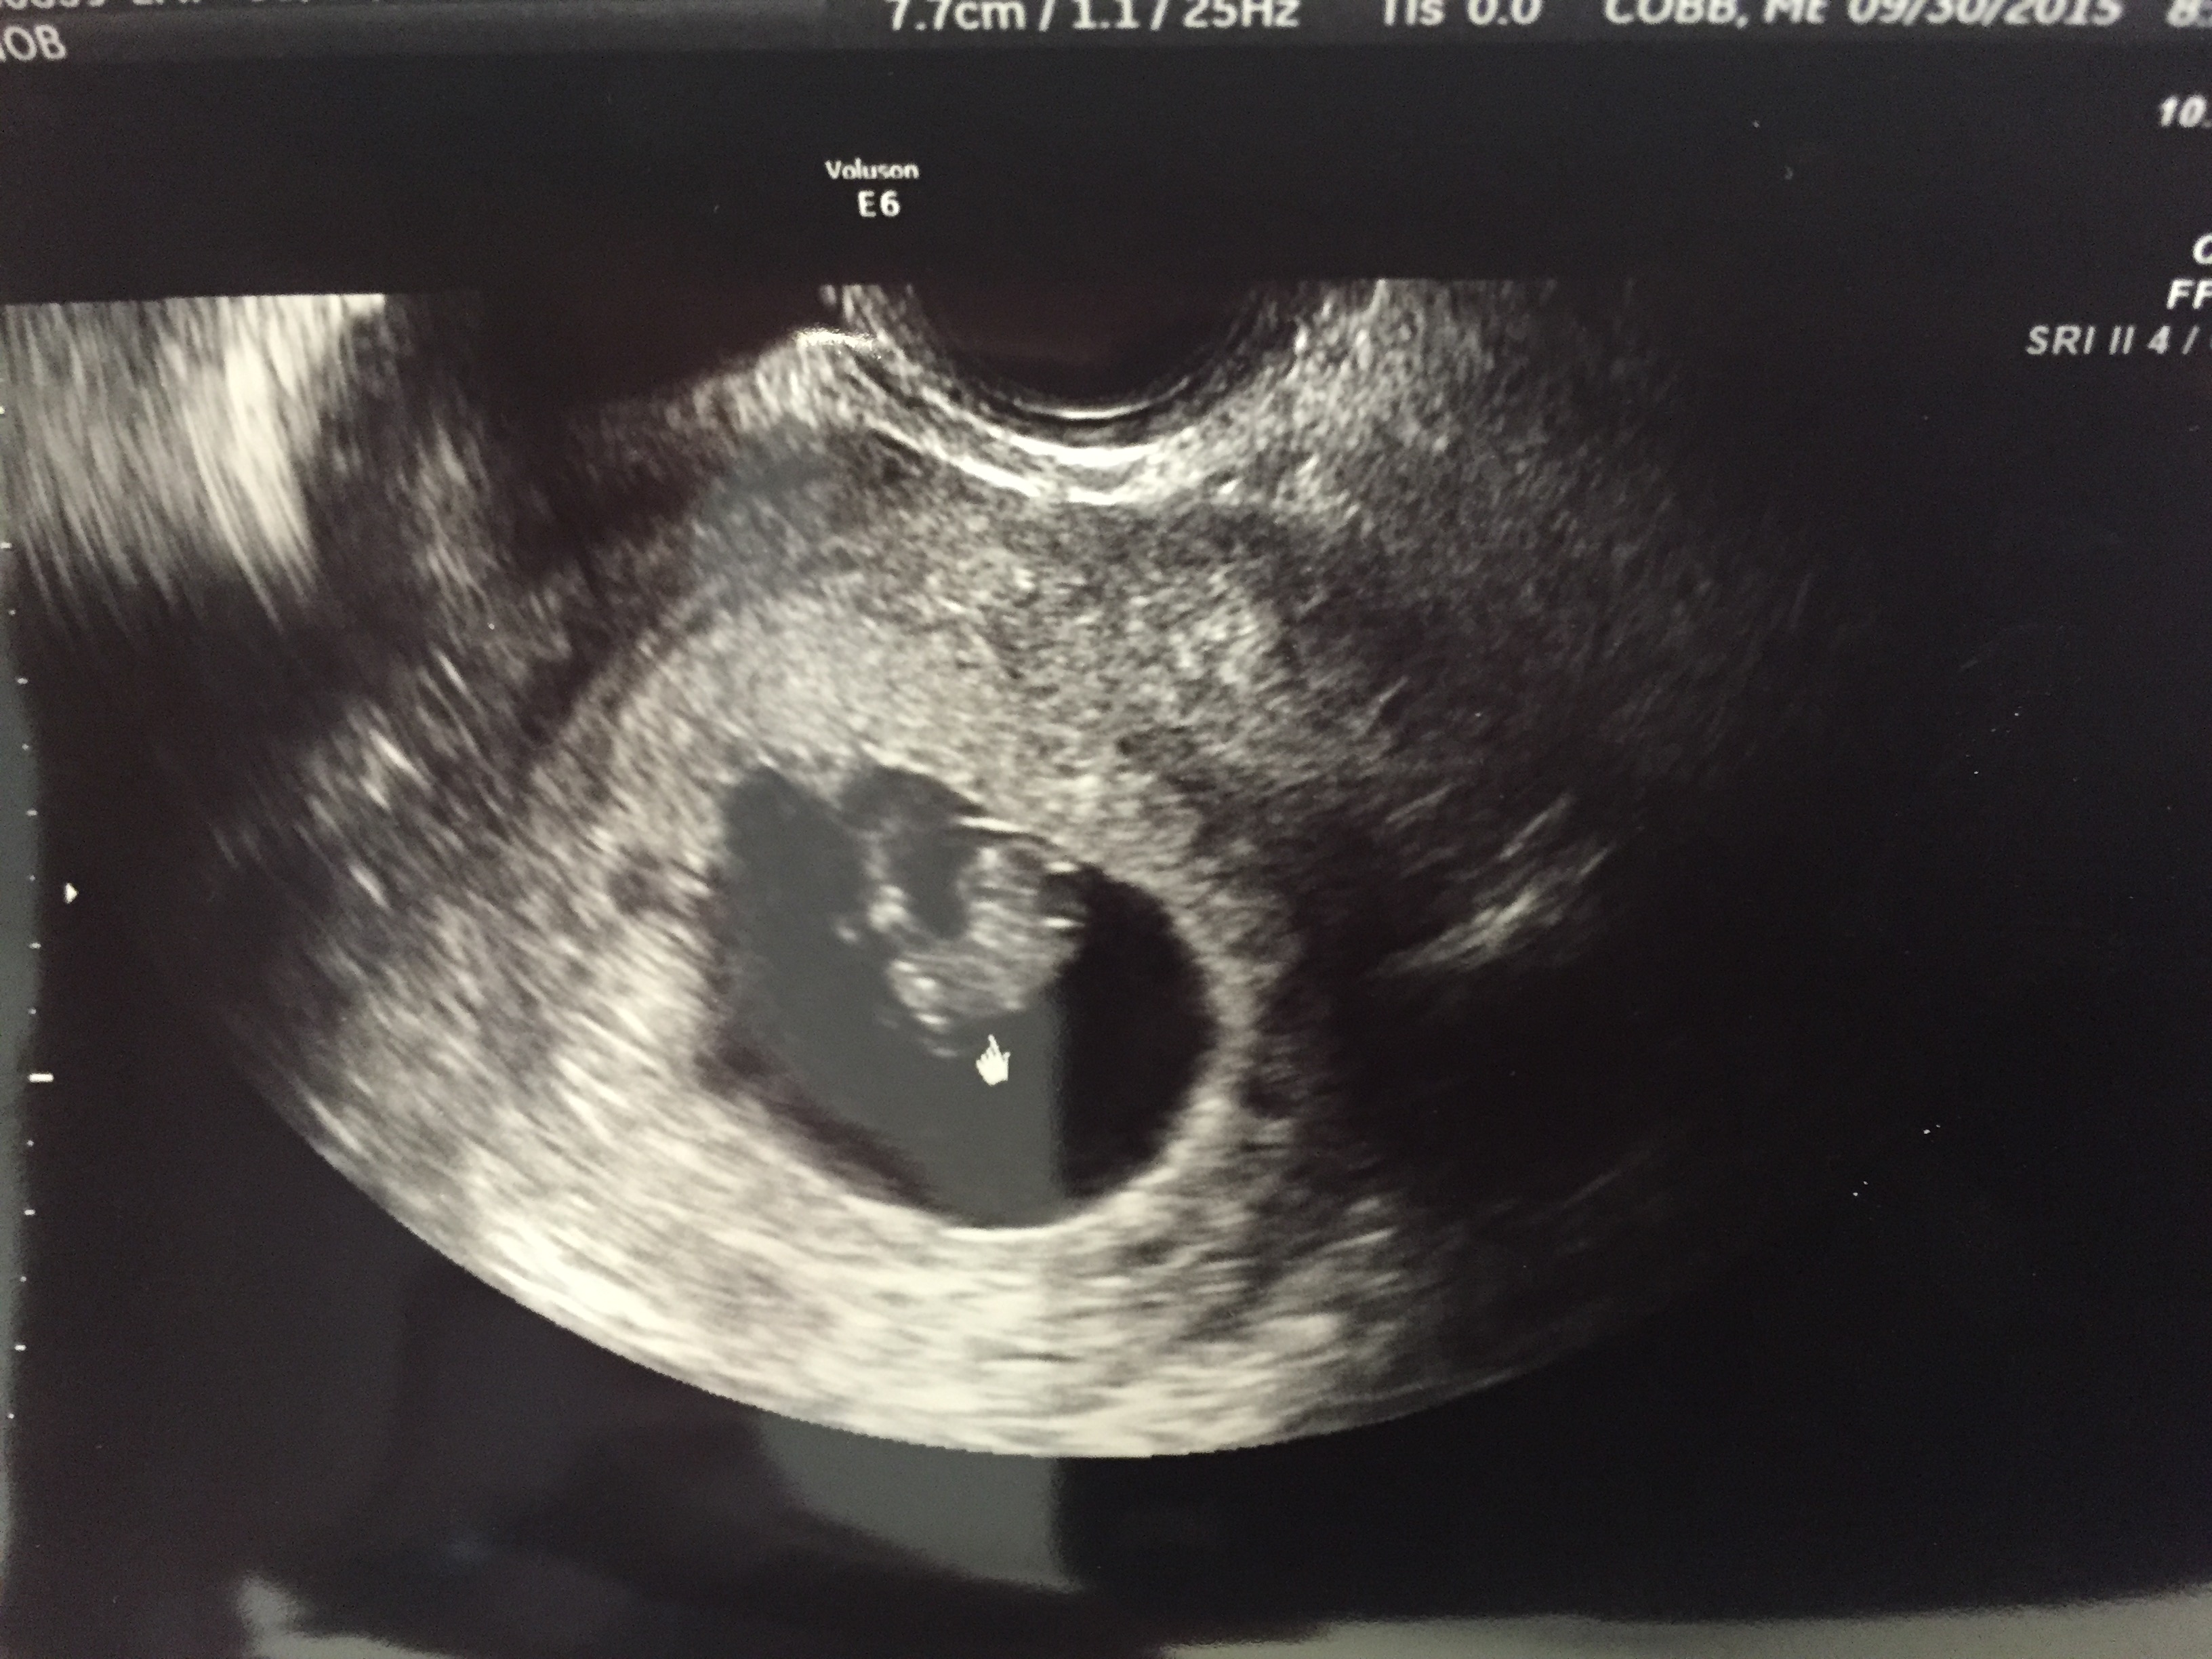

Here is my little one! We are 7 weeks 4 days baby was measuring 7 weeks 1 day and the heartbeat was 128bpm! Best thing ever to see that little heart flicker!